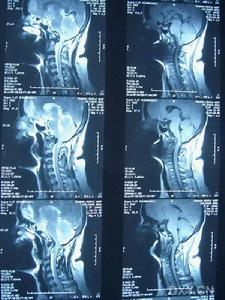

(1)大小:淋巴結的大小是評價頸部淋巴結的最基本的標準。CT在測量淋巴結大小方面具有優越性,尤其對強化明顯的淋巴結。大多數學者以淋巴結的長徑10~15mm為標準,亦有以淋巴結的短徑8~10mm為標準者,經統計學處理兩個診斷標準有顯著差異。作者以Ⅱ、Ⅲ、Ⅳ區腫大淋巴結直徑≥15mm,其他區域直徑≥10mm為診斷頸部淋巴結腫大的標準。敏感性為84.6%,特異性為86.7%,診斷失誤濾在10%~20%。作者認為若以較大徑為診斷標準則可提高其特異性,但降低其敏感性,反之,若以較小徑為診斷標準則可提高其敏感性,降低特異性,所以任何以大小作為診斷標準均有假陽性、假陰性可能。有學者提出不論淋巴結的大小,只要淋巴結內部密度有改變且邊緣較清晰者均應判定為轉移淋巴結。

(2)部位:頸部淋巴結轉移癌為頸部最常見的淋巴結病變,以中、老年男性多發,可發生在單側或多側,雙側多見,頸部Ⅱ~Ⅳ區為好發區,此區發生率約92%,與原發腫瘤有關,最多見為鼻咽癌、口咽癌和甲狀腺癌,其中咽後、頸後三角區為鼻咽癌的特徵性部位;甲狀腺癌常見於Ⅲ、Ⅳ區,且可發生氣管食管溝、上縱隔淋巴結轉移;淋巴瘤在頸部淋巴結病變第二位,發病年齡、性別無差異,以非霍奇金病常見,常以雙側或多側、多區、多個淋巴結受累為主要表現,本組病例中各區發生率無顯著差異;頸部淋巴結結核多為結核桿菌經淋巴通路感染而成,好發於年輕女性,常位於單側或多側多區,可以侵犯頸靜脈周圍和後三角區,本組以Ⅲ~Ⅴ區受累多見,尤其Ⅳ區+鎖骨上區明顯,約占75%;淋巴結炎、化膿性淋巴結炎往往合併咽喉炎、扁桃體炎和頭面部皮膚炎症,Ⅰ區為好發部位。

(3)形態:有學者提出增大淋巴結的最長徑與短徑之比>2為正常反應性增生的淋巴結,而<2時則提示為淋巴結轉移。本文採用此標準,其特異性為86.5%,準確性為85.4%。頸部轉移性淋巴結易融合,本組發生率71%,其中1例直腸癌術後淋巴結轉移出現鈣化;淋巴瘤常多個融合成團塊狀,本組5例中有4例融合,鈣化少見;淋巴結結核鈣化常見,本組8例3例出現鈣化,呈斑塊或蛋殼樣鈣化,3例出現融合改變;非特異性淋巴結炎和化膿性淋巴結炎往往呈單個腫大淋巴結,融合、鈣化少見。

(4)邊緣:轉移性淋巴結輪廓表現為清晰或模糊,本組28例清晰為9例,多為甲狀腺癌、鼻咽癌;模糊17例(60.7%),多為喉癌、口咽癌和下咽癌。其中8例最小徑>6cm的淋巴結均有包膜外侵犯(100%),11例最小徑為3~6cm的淋巴結有5例為包膜外侵犯(45.4%),6例最小徑為1.5~3cm的淋巴結有2例包膜外侵犯(33.3%);淋巴瘤包膜外侵犯少見,多見於最小徑>6cm的淋巴結,本組5例中3例邊緣模糊,最小徑均>6cm,且呈融合改變。活動期淋巴結結核周圍可見炎性滲出性改變,周圍間隙模糊不清,具有特徵性。非特異性淋巴結炎和化膿性淋巴結炎因長期炎症刺激,使其被膜已與周圍軟組織發生炎性粘連,出現邊緣模糊。

(5)強化特徵:轉移性淋巴結癌、淋巴結結核及化膿性淋巴結炎在CT圖像上均易表現邊緣強化,中央壞死呈囊狀改變。文獻報導,不規則環行強化伴中央低密度影為鱗癌轉移淋巴結的CT特徵性表現,如有原發腫瘤時此徵象的特異性幾乎為100%。作者以此為診斷標準,其特異性為97.2%,準確性為98%。甲狀腺乳頭狀癌的特徵性改變為淋巴結囊性變及壁內明顯強化的乳頭狀結節,本組7例乳頭狀瘤中,出現5例(71%)。而多環狀強化或分房樣強化、中心壞死,可伴有周圍肌肉膿腫,周圍脂肪層模糊,內部見點狀鈣化為頸部淋巴結結核的典型表現。本組28例中15例基本符合此種表現。化膿性淋巴結炎大多為單發,環狀均勻強化、壁厚,無明顯壁結節和鈣化。淋巴瘤常為均勻強化,邊緣環狀強化少見,本組1例惡性淋巴瘤患者化療後出現中央壞死、邊緣強化。